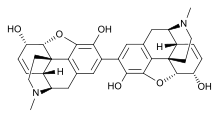

The pharmacodynamic response to an opioid depends upon the receptor to which it binds, its affinity for that receptor, and whether the opioid is an agonist or an antagonist. For example, the supraspinal analgesic properties of the opioid agonist morphine are mediated by activation of the μ1 receptor; respiratory depression and physical dependence by the μ2 receptor; and sedation and spinal analgesia by the κ receptor. Each group of opioid receptors elicits a distinct set of neurological responses, with the receptor subtypes (such as μ1 and μ2 for example) providing even more [measurably] specific responses. Unique to each opioid is its distinct binding affinity to the various classes of opioid receptors (e.g. the μ, κ, and δ opioid receptors are activated at different magnitudes according to the specific receptor binding affinities of the opioid). For example, the opiate alkaloid morphine exhibits high-affinity binding to the μ-opioid receptor, while ketazocine exhibits high affinity to ĸ receptors. It is this combinatorial mechanism that allows for such a wide class of opioids and molecular designs to exist, each with its own unique effect profile. Their individual molecular structure is also responsible for their different duration of action, whereby metabolic breakdown (such as N-dealkylation) is responsible for opioid metabolism.

Several semi-synthetic opioids were developed in Germany in the 1910s. The first, oxymorphone, was synthesized from thebaine, an opioid alkaloid in opium poppies, in 1914.[228] Next, Martin Freund and Edmund Speyer developed oxycodone, also from thebaine, at the University of Frankfurt in 1916.[229] In 1920, hydrocodone was prepared by Carl Mannich and Helene Löwenheim, deriving it from codeine. In 1924, hydromorphone was synthesized by adding hydrogen to morphine. Etorphine was synthesized in 1960, from the oripavine in opium poppy straw. Buprenorphine was discovered in 1972.[228]

Morphinan derivatives